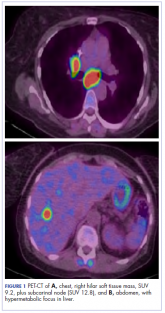

ArticleStriking rash in a patient with lung cancer on a checkpoint inhibitorAuthor:Tanios et alPublish date: June 21, 2018Read More